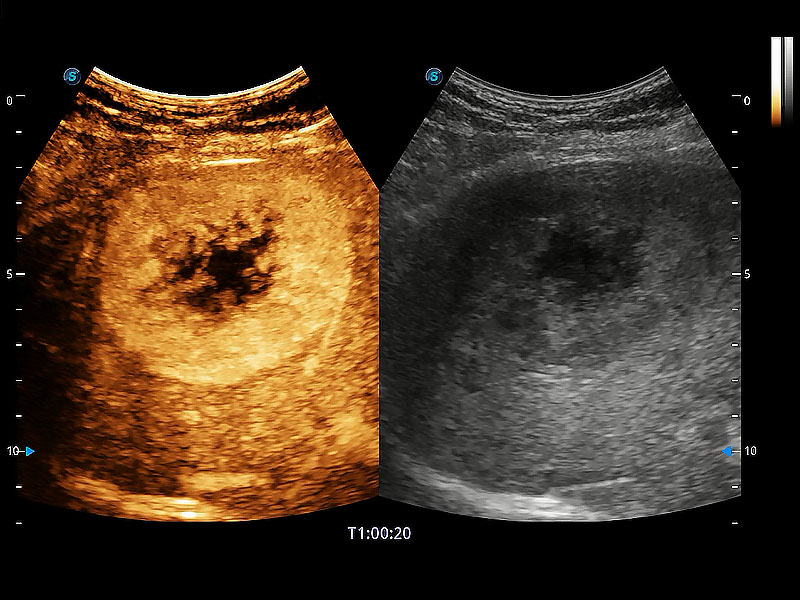

非线性融合造影成像充分利用谐波和基波信号,为难以观察的血流进行增强显像。可用于线阵、凸阵、微凸阵、相控阵探头。

高性能和先进的临床应用工具可以为动物医生提供临床信心。ProPet 80 搭载了先进的腹部和浅表应用工具,帮助医生在日常临床实践中发挥前所未有的作用。